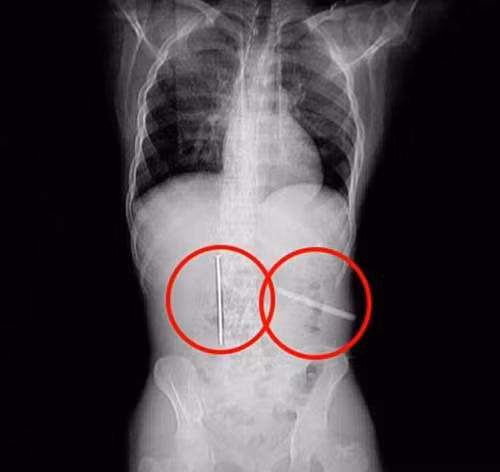

Lúc tiến hành chụp X-quang cho bệnh nhân, các bác sĩ đều vô cùng bất ngờ khi nhìn thấy ảnh hai dị vật. Chiếc đinh và lưỡi cưa cắm sâu vào hai vị trí khác nhau trong dạ dày Gong. Các bác sĩ lập tức tiến hành phẫu thuật và cuối cùng lấy thành công những "món đồ" trên sau hai giờ.